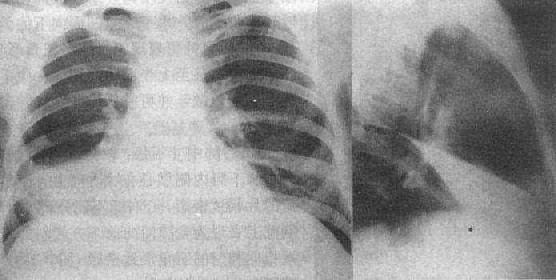

(1)一侧性肺不张:X线现为患侧肺野均匀致密,纵隔向患侧移位,肋间隙变窄(图3-1-7)。健侧肺可有代偿性肺气肿。

一侧性肺不张

图3-1-7 一侧性肺不张

左侧支气管阻塞引起左侧全肺不张,显示左侧肺野均匀致密,

纵隔向患侧移位,肋间隙变窄,膈升高